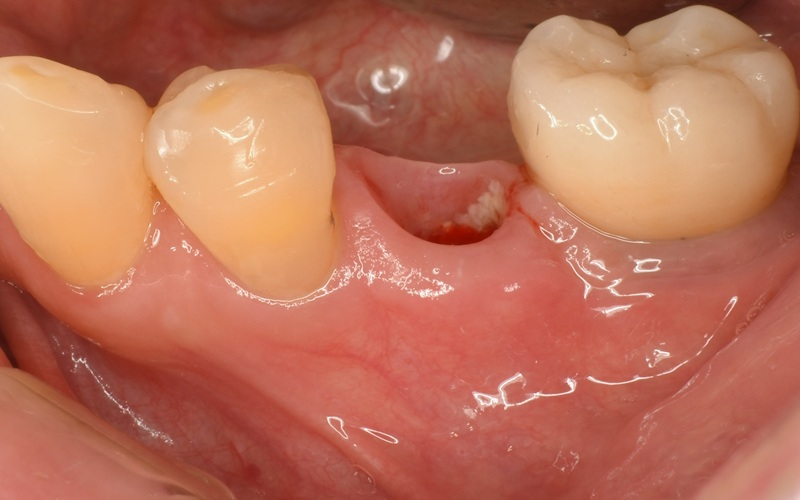

Case7

術前

術中

術後

| 治療名 | 抜歯即時インプラントとソケットリフトによる上顎臼歯部の修復症例 |

|---|---|

| 治療説明 |

歯の根が破折していたため抜歯が必要となり、患者さんとご相談のうえ、インプラントによる治療を選択しました。 ただし、インプラントを支える骨の高さが不足していたため、**上顎洞に骨を足す“ソケットリフト”**を併用し、安全にインプラントを埋入しました。 |

| 治療回数・期間 | 約3ヶ月 |

| 副作用とリスク |

・入れ歯や従来のブリッジと比べて、治療期間が長くなる傾向があります。 |

| 料金(税込) | 小規模GBR:110,000円 ソケットリフト:165,000円 インプラント一次手術:220,000円 二次手術:55,000円 上部構造〈セラミック〉:165,000円 合計:715,000円 |